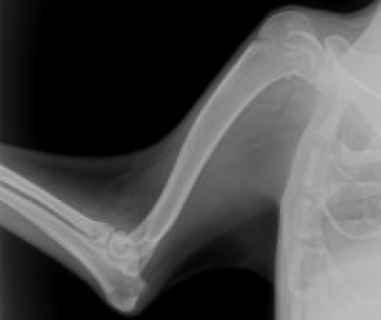

На рентгенограмме - выраженный остеопороз (разряжение костной ткани). Также проводятся: термография, сцинтиграфия, магнито-резонансная томография, денситометия, контрактурометрия.